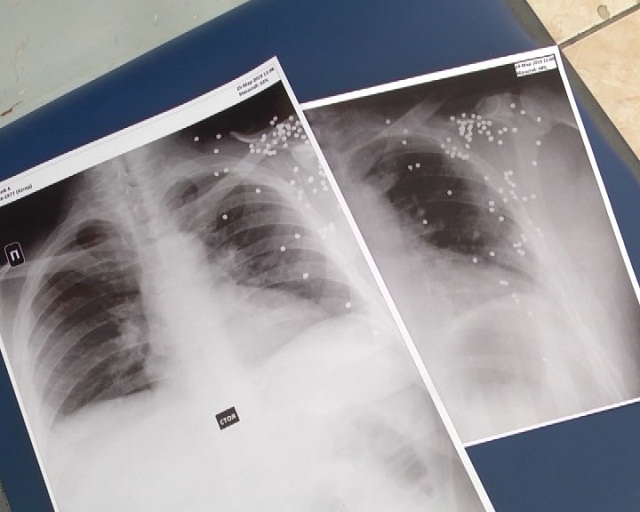

Виталий вспоминает, собрав волю в кулак, вышиб запертую дверь. Знакомый уже сидел за рулем его автомашины. Пострадавший добежал до сторожки гаражного кооператива, а его обидчик скрылся. Шокированный Виталий потерял сознание только на хирургическом столе. Врачи говорят, жизненно-важные органы не задеты, повреждены лишь мягкие ткани и мышцы. Внутри остались осколки.

— Огнестрельные ранения, чаще всего, обычно тяжело проходят, но в данном случае повезло то, что ранение пошло по телу лопатки, что и, в принципе, спасло жизнь, — отметил Серик Искаков, старший врач-ординатор отделения политравм больницы № 1 города Павлодара.